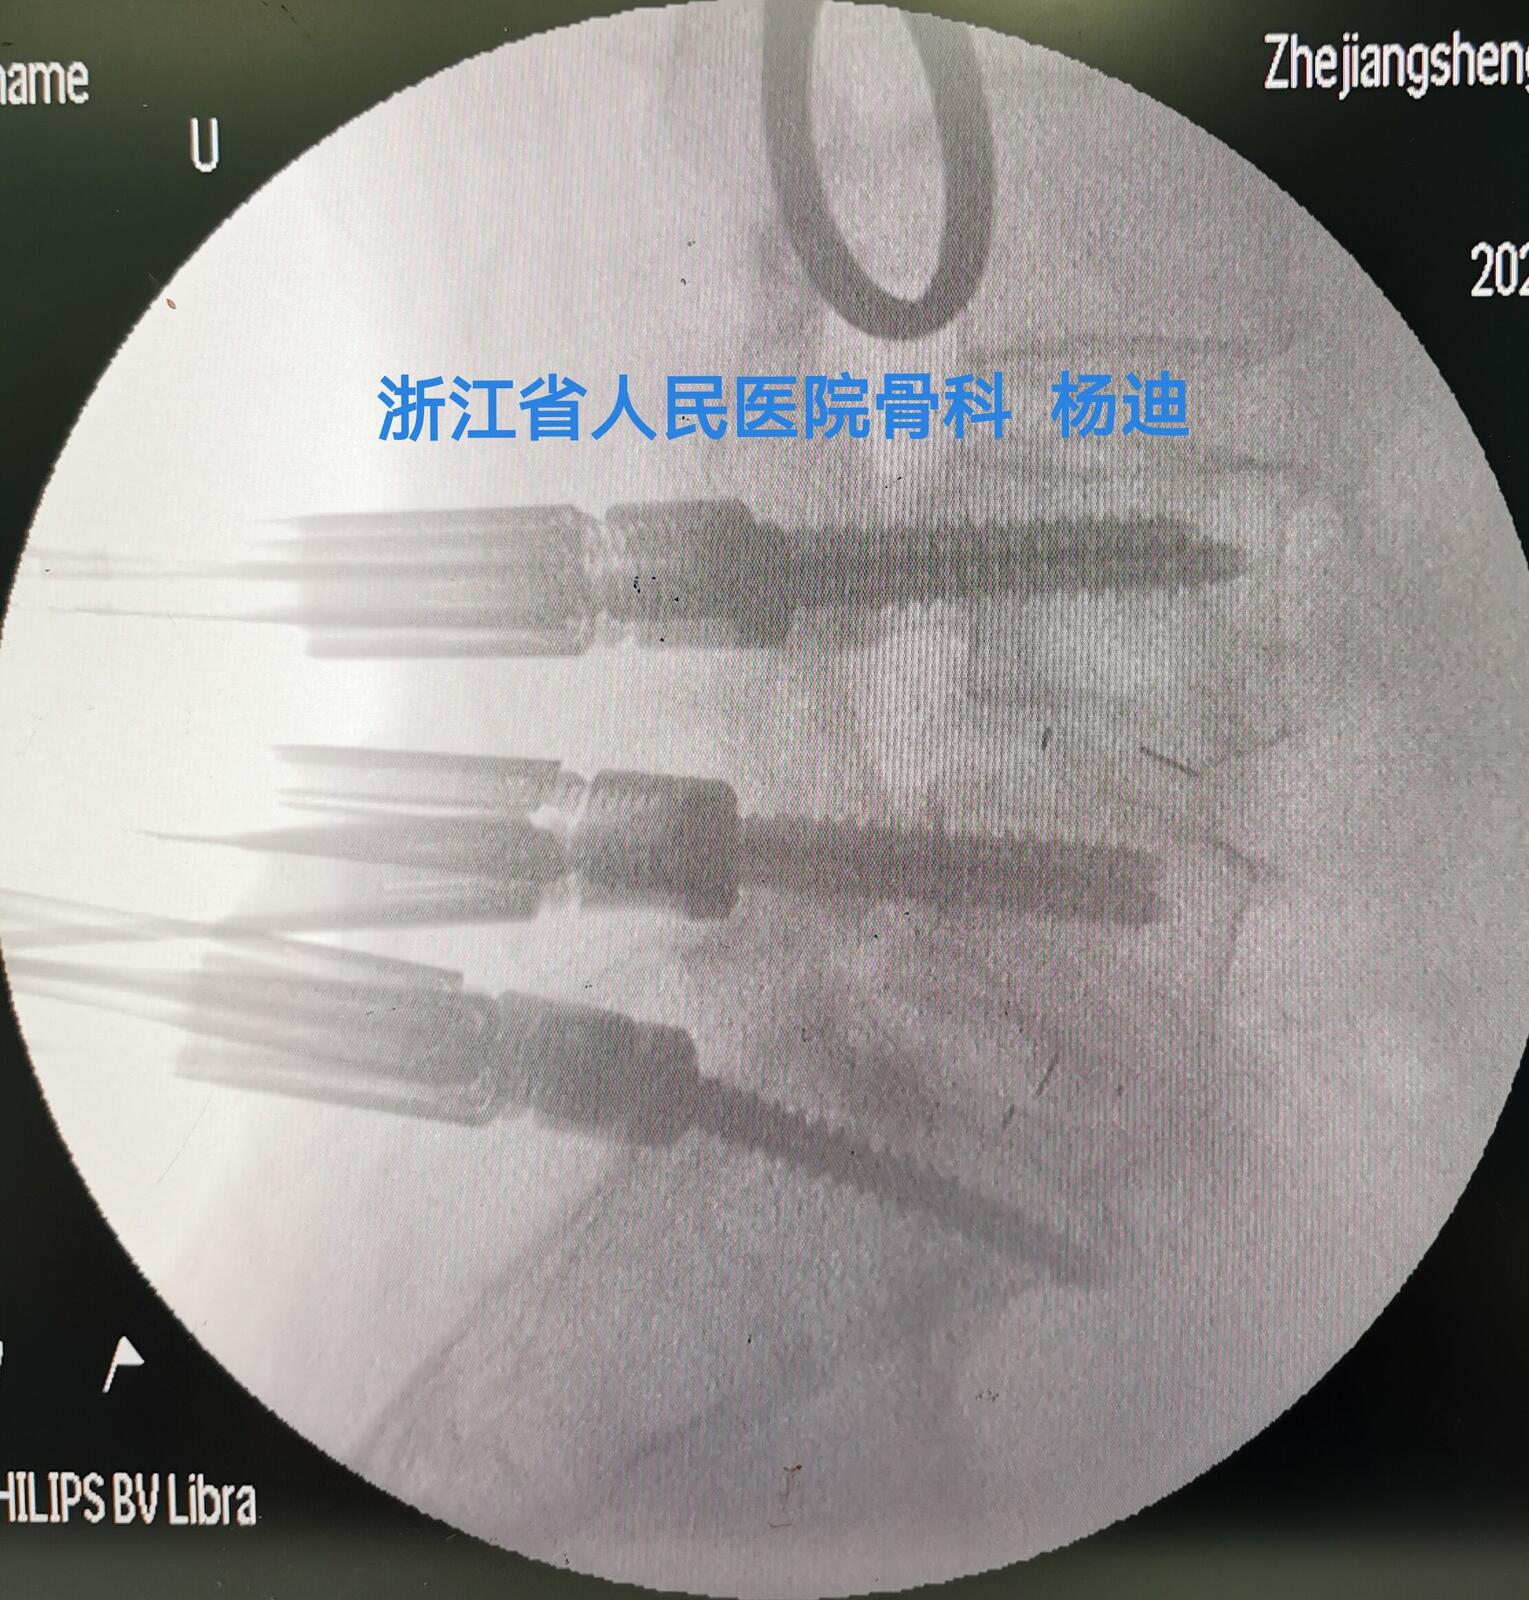

患者于全麻下行“微创后路腰4/5、腰5/骶1减压椎间植骨融合内固定术”,手术经过顺利,术中出血约100ml。术后患者下肢疼痛即刻消失、麻木明显好转,四肢活动良好、肌力V级。术后2天拔除伤口引流管,佩戴腰部支具下床活动。伤口愈合良好,未出现感染,满意出院。

图为腰4/5、腰5/骶1减压椎间融合器置入、经皮螺钉置入后,C臂透视见融合器及螺钉位置、长度满意。

图为腰4/5、腰5/骶1减压椎间融合器置入、经皮螺钉置入后,C臂透视见融合器及螺钉位置、长度满意。